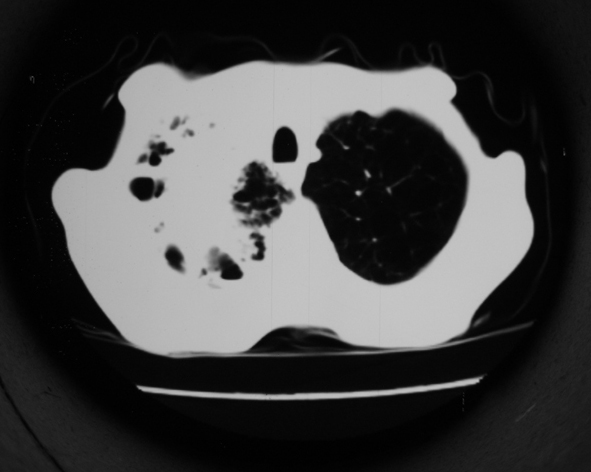

男53岁,咳嗽气短,以往身体健康.

右肺上叶多发多形态空洞及增殖灶,可见团块钙化,胸膜肥厚、粘连,考虑继发型肺结核可能性大

1.右肺上叶干酪性肺炎,2。肺气肿,肺大泡

支持:继发型肺结核合并干酪性肺炎

1.右肺上叶干酪性肺炎,2。肺气肿,肺大泡。支持!

支持右上肺继发性肺结核并干酪性肺炎,右肺大泡,左肺代偿性气肿。